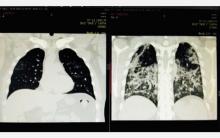

Сергей Лукьянов: «COVID-19 - это такая особая форма заболевания, называемая коронавирусом, которая чаще всего проявляется пневмонией, и эта пневмония, от которой все умирают, которая, собственно, является краеугольным камнем, сутью этой болезни. Это проявление заболеваний: у кого-то может быть бессимптомная форма - пневмонии нет, только болит горло, заложен нос, нет обоняния, вкуса (это лёгкая форма COVID-19). Средней степени - это когда есть пневмония, но человек не нуждается в кислороде, и тяжёлая форма - когда пневмония поражает 50% лёгких и более, у человека возникает потребность в кислороде и в искуственной вентиляции лёгких».